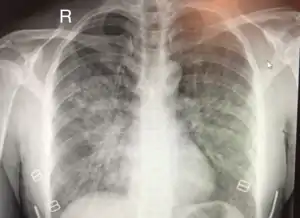

| Chest x-ray of HAPE showing characteristic patchy alveolar infiltrates with right middle lobe predominance. | |

On physical exam, increased breathing rates, increased heart rates, and a low-grade fever 38.5o (101.3o F) are common.[8][3] Listening to the lungs may reveal crackles in one or both lungs, often starting in the right middle lobe.[8][3] Imaging studies such as X-ray and CT imaging of the chest may reveal thoracic infiltrates that can be seen as opaque patches.[13][8][3] One distinct feature of HAPE is that pulse oximetry saturation levels (SpO2) are often decreased from what would be expected for the altitude. People typically do not appear as ill as SpO2 and chest X-ray films would suggest.[8][3] Giving extra oxygen rapidly improves symptoms and SpO2 values; in the setting of infiltrative changes on chest X-ray, this is nearly pathognomonic for HAPE.[3]

Hypoxic pulmonary vasoconstriction (HPV) occurs diffusely, leading to arterial vasoconstriction in all areas of the lung. This is evidenced by the appearance of "diffuse," "fluffy," and "patchy" infiltrates described on imaging studies of climbers with known HAPE.[8]